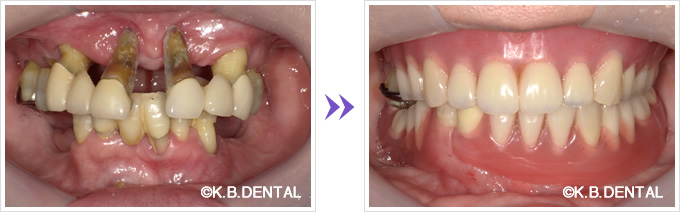

インプラント4本によるインプラントオーバーデンチャー

正面:インプラントオーバーデンチャー

嘔吐反射が酷くブラッシングなどのセルフケアが難しい症例です(インプラントと義歯内面のマグネットで無口蓋金属床義歯ノンクラスプライプを維持しています)。

保存可能な歯牙は可及的に残し、クラスプと呼ばれる歯にかけるバネを使用しないため、残存歯の感覚も残しながらインプラントオーバーデンチャーによる咬合負担も可能にした症例。

咬合調整により天然歯と義歯の被圧変異量の差を考慮した調整が必要なため、装着時に細かい調整が必要ですが、長期的に安定した状態を得ることができます。

また義歯は外して義歯洗浄剤を使用し、残存歯とインプラント部は前方に集中しているため、嘔吐反射の患者さんでも手入れが容易でメンテナンスしやすい構造となっております。

年齢/性別 50代男性

治療期間 約6ヶ月

費用 約200万円(税別)